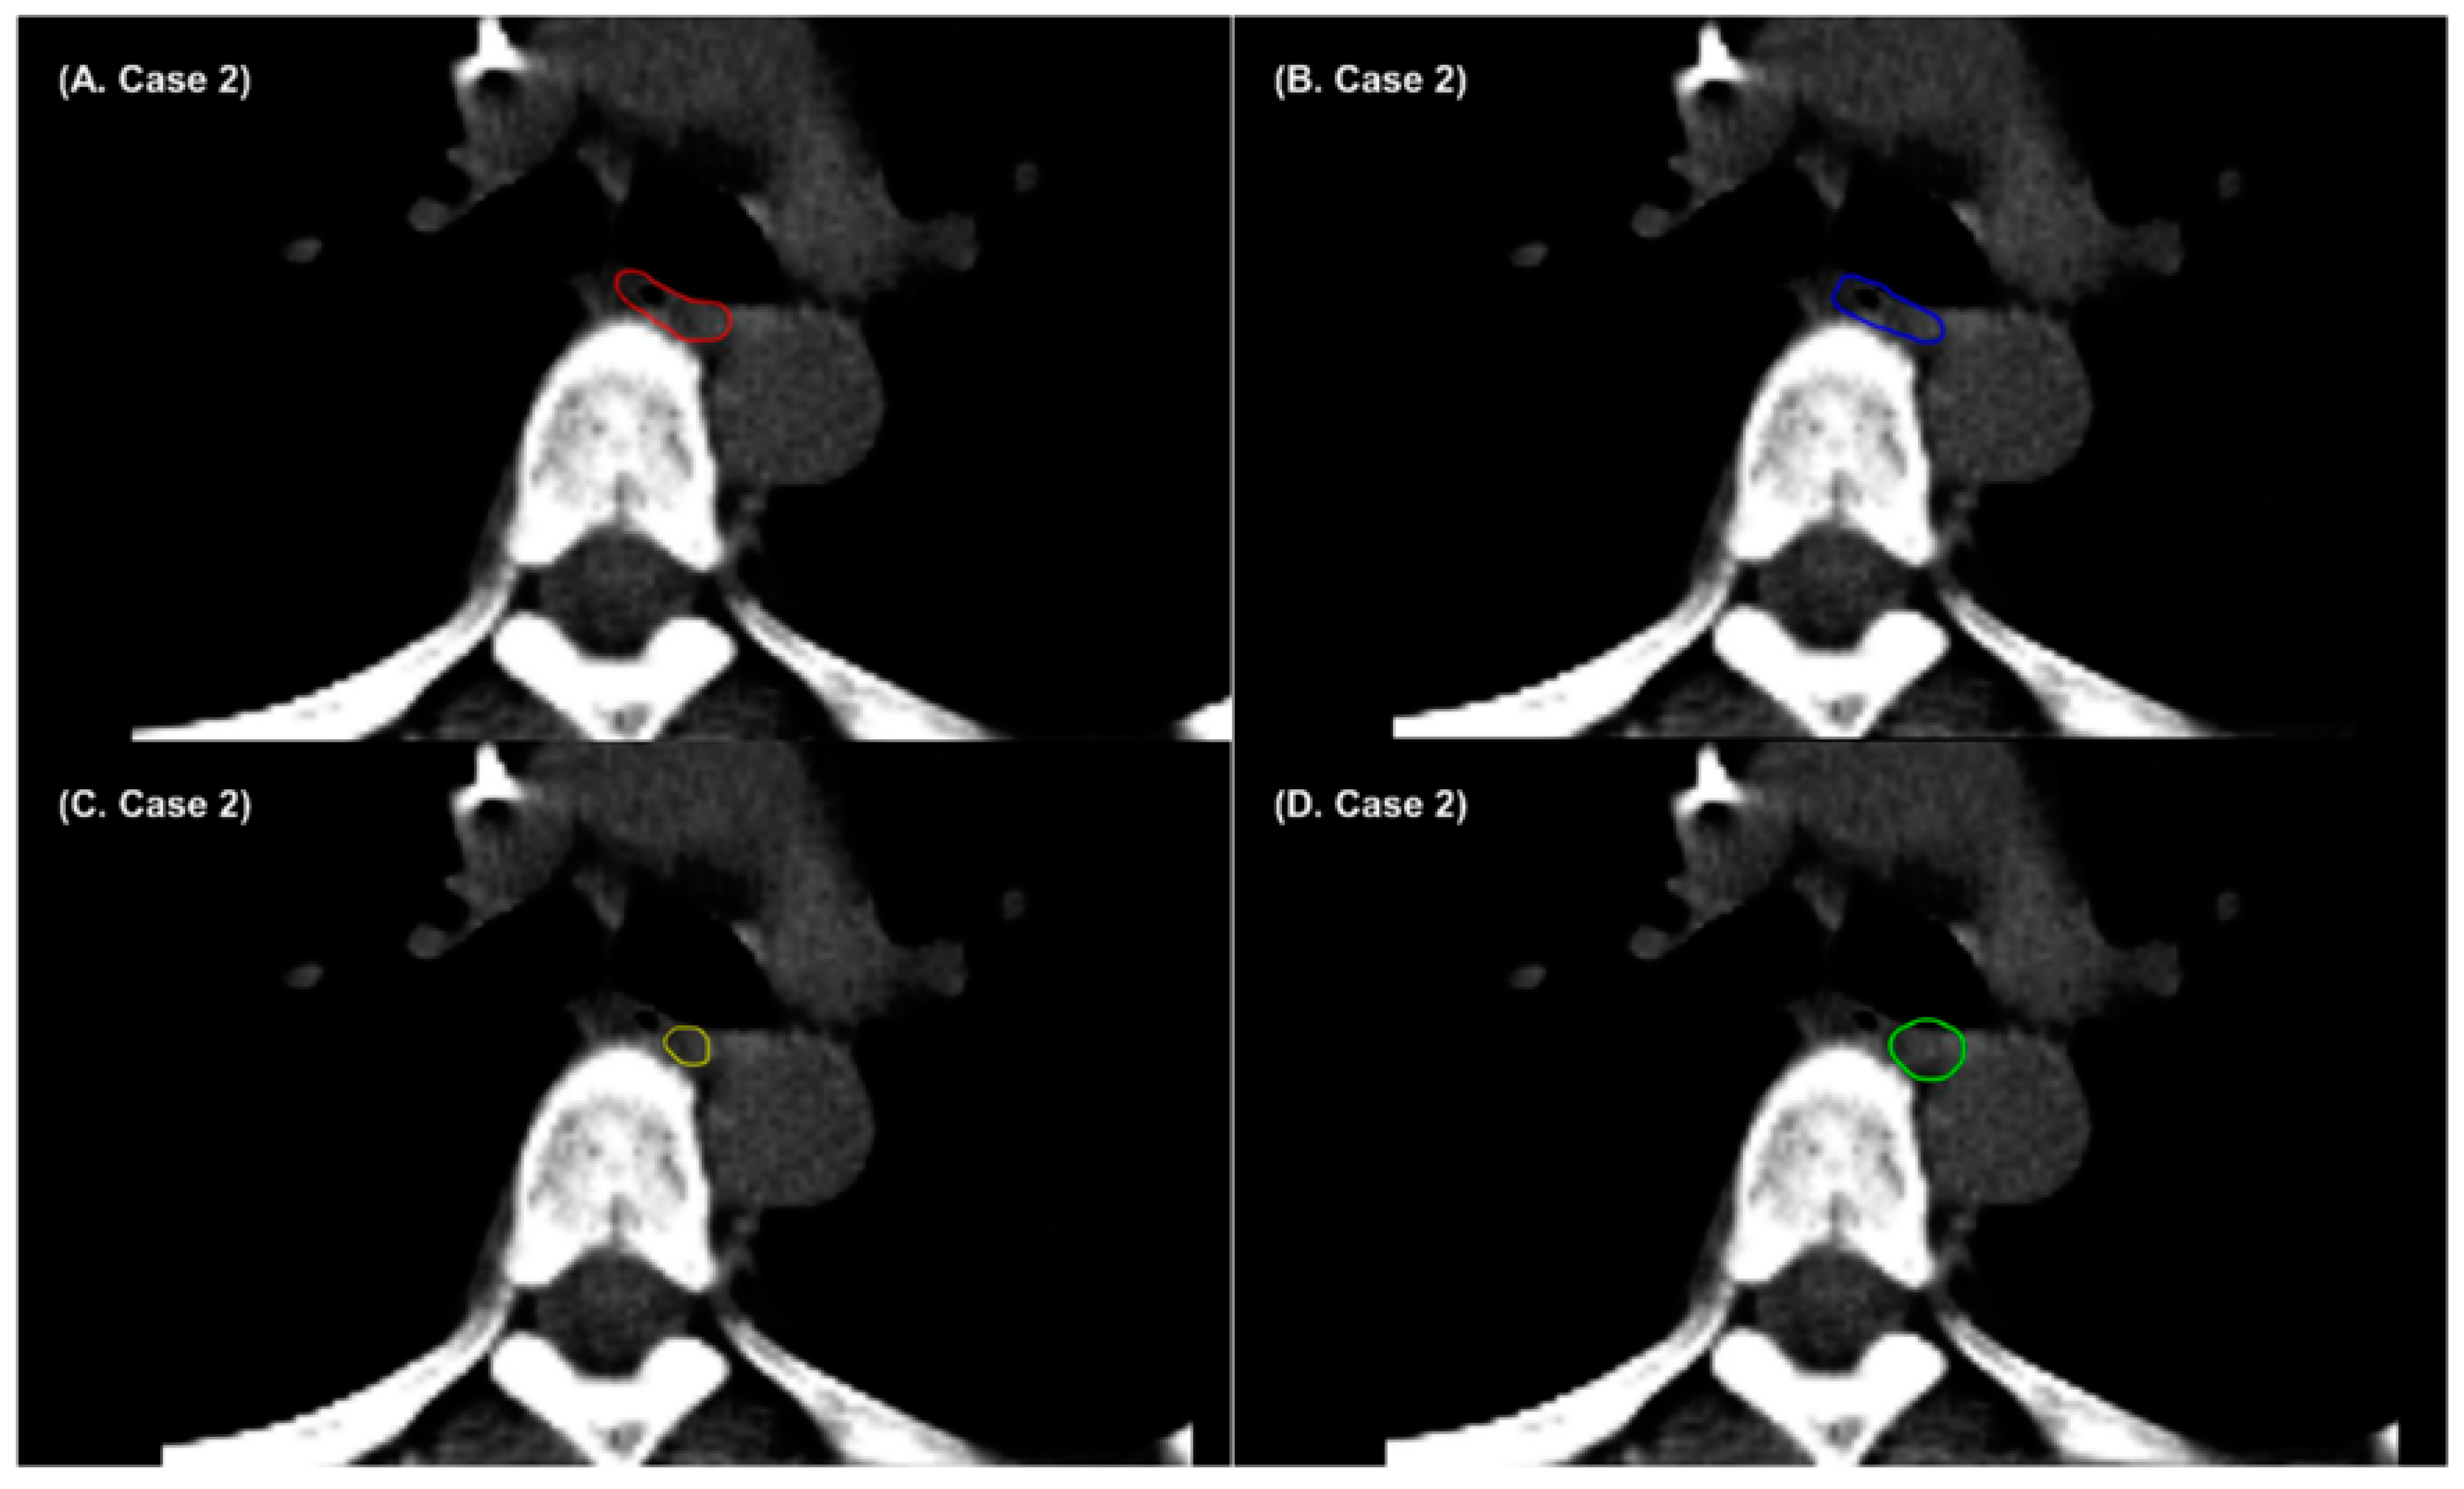

- Chung, S.Y.; Chang, J.S.; Choi, M.S.; Chang, Y.; Choi, B.S.; Chun, J.; Keum, K.C.; Kim, J.S.; Kim, Y.B. Clinical feasibility of deep learning-based auto-segmentation of target volumes and organs-at-risk in breast cancer patients after breast-conserving surgery. Radiat. Oncol. 2021, 16, 1–10. [Google Scholar] [CrossRef] [PubMed]

- Choi, M.S.; Choi, B.S.; Chung, S.Y.; Kim, N.; Chun, J.; Kim, Y.B.; Chang, J.S.; Kim, J.S. Clinical evaluation of atlas-and deep learning-based automatic segmentation of multiple organs and clinical target volumes for breast cancer. Radiother. Oncol. 2020, 153, 139–145. [Google Scholar] [CrossRef]